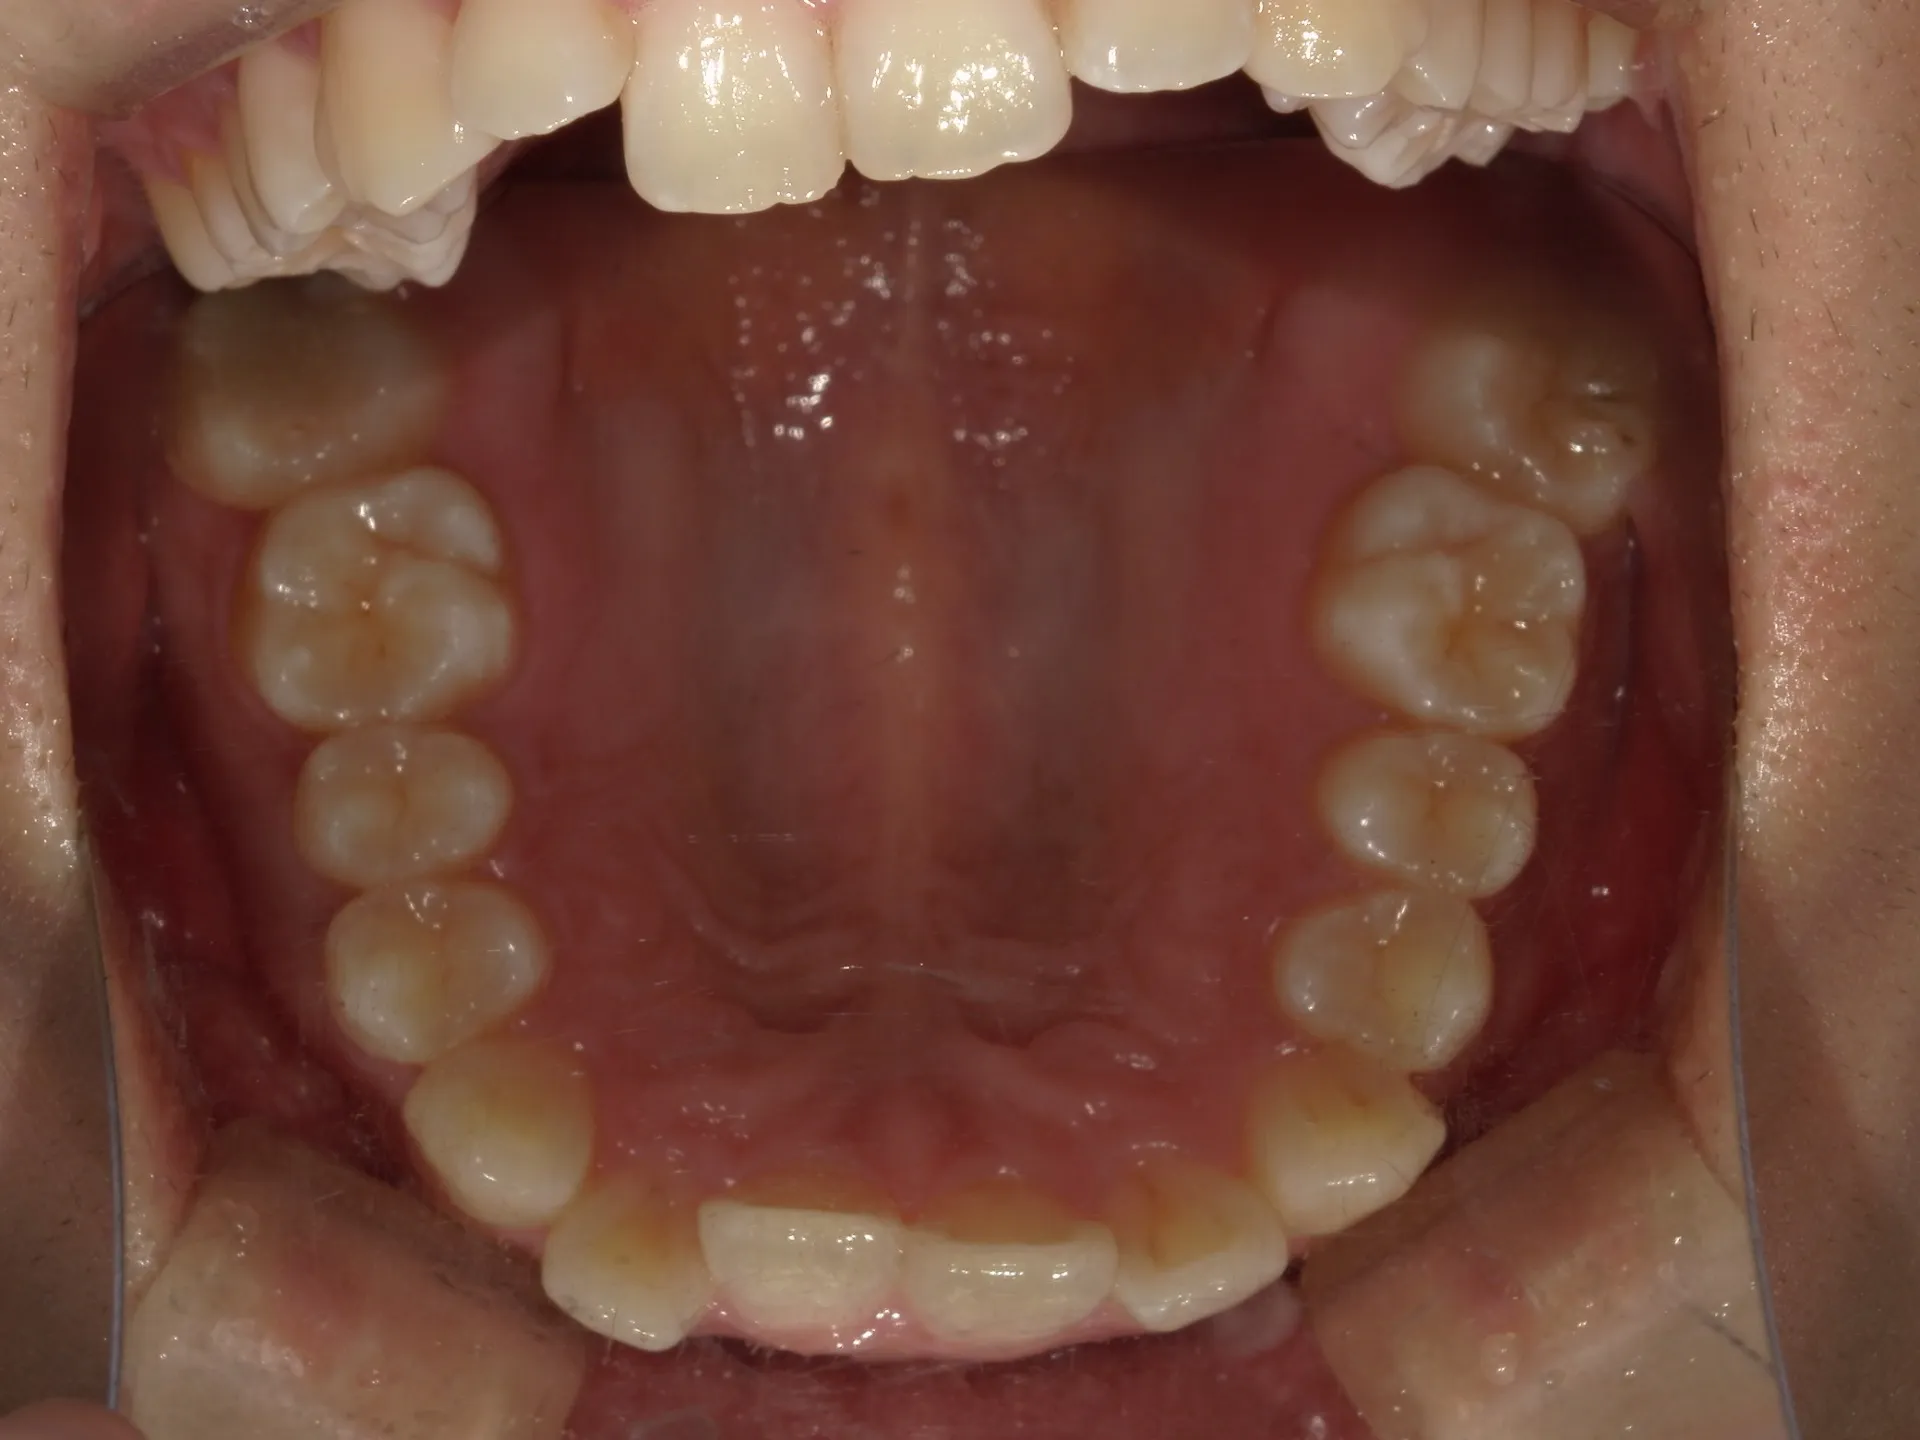

前歯が内側に倒れてたりしませんか?

または2番目の歯が外側に飛び出していませんか?

この2つはよく同時に起こることがあります。

今回はインビザライン矯正治療(マウスピース矯正)で治療した症例についてご紹介いたします。